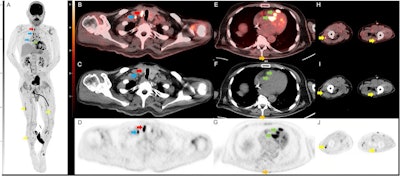

The whole-body FDG-PET/CT scan demonstrated multiple markedly hypermetabolic lymph nodes throughout the body, including a hypermetabolic 2 cm by 1.4 cm thyroid nodule, as well as marked global hypometabolism in the brain. A subsequent biopsy of the lymph nodes was nondiagnostic, but a thyroid biopsy tissue yielded a diagnosis of sarcoid, according to the report.

"This result, coupled with the PET/CT findings, suggested the diagnosis of sarcoid with neurologic, thyroid, and likely cardiac involvement," the group wrote.